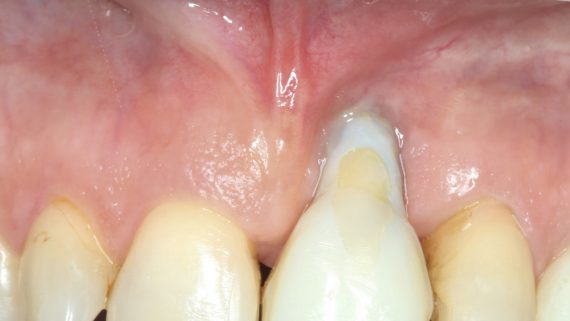

Обычно следующим этапом является формирование десневой манжеты, установка формирователей десны или мукогингивопластика. Последнюю можно начать и раньше, поскольку она не предполагает какой-либо нагрузки на имплантат или доступа к регенерату: